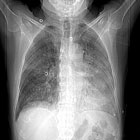

Une pneumonie subaiguë

Pr Jean-Louis Pujol CHU et IRCM INSERM U 1194 - Montpellier

Solution du cas

Il s’agit d’un adénocarcinome pulmonaire. L’hypothèse est renforcée par une positivité franche du marquage nucléaire par le TTF1.

La présentation clinique très préoccupante rend impossible un traitement par chimiothérapie.

Alors que le patient est encore en réanimation, à J2, un traitement par erlotinib 150 mg (inhibiteur de la tyrosine kinase du récepteur de l’EGFR) est débuté.

Tous les paramètres cliniques...